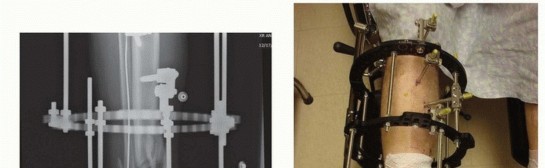

Knee-Spanning Fixator of Tibial Plateau Fracture Two Schanz pins are placed along the anterolateral thigh. These pins are placed in the midshaft region of the femur ( TECH FIG 5). Two Schanz pins are then inserted into the midshaft and distal tibia. Apply the tibial pins far enough away from the distal extension of the proximal tibia such that any future incisions required to perform definitive open reduction and internal fixation of the plateau fracture would not impinge on the pins.

### TECH FIG 5 • A. Open tibial plateau to be stabilized with knee-spanning fixator. B. Following a gentle manual reduction, the proposed location for eventual fixation incisions, as well as proposed pin sites, are marked on the skin. C. Two pins each above (distal femur) and below (mid tibia) the plateau fracture zone of injury are applied.

A solitary bar can then be used to span all pins. Longitudinal traction is applied and reduction confirmed under fluoroscopy. Slight flexion of the knee is maintained and all connections are tightened to maintain the ligamentotaxis reduction. Alternatively, the proximal two femur pins can be connected using a single bar and the two tibial pins with a second bar. These two bars can then be manipulated to achieve a reduction of the plateau, and a third bar connecting the proximal femoral and distal tibial bars is then attached and tightened to maintain the reduction. A large monotube fixator can also be used in this fashion to span the knee and maintain a temporary reduction. 542

### TECH FIG 5 •

D,E. One single bar connects the proximal two pins to the distal two pins. The fracture is then reduced and the clamps tightened. A second bar was added for stability, bridging the fracture.